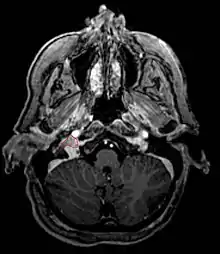

Glomus Jugulare

- Commonly arise from the paraganglia of the jugular bulb

- Typically invade the tympanic cavity and jugular foramen

- Can extensively invade petroclival region

- Can invade cavernous sinus above

- Can invade hypoglossal canal below

- Clinical presentation typically with tinnitus or hearing loss, but may also impact jugular foramen CNs